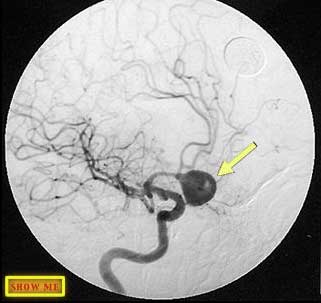

Can you see a large aneurysm?

click to view answer